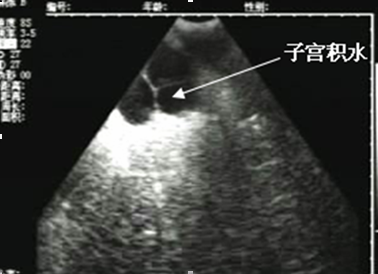

二、子宫内膜多厚才算正常呢?

每次月经,其实都是子宫内膜在发生变化,那么,是不是每一次月经之后子宫内膜都会变薄呢?其实不然。子宫内膜其实是由基底层和功能层组成的,基底层不受月经周期中卵巢激素变化的影响,在月经期不发生脱落;而功能层则受卵巢激素的影响呈现周期性变化,月经期就会出现坏死脱落现象。

所以,每个月正常子宫内膜厚度都是处于不断变化中的。在月经期的时候,由于子宫内膜功能层脱落保留基底层,一般厚度比较小,约5mm左右。在月经第6-14天,内膜厚度低至1-3mm,而在月经第15-28天,子宫内膜又会恢复到5-7mm左右的厚度。